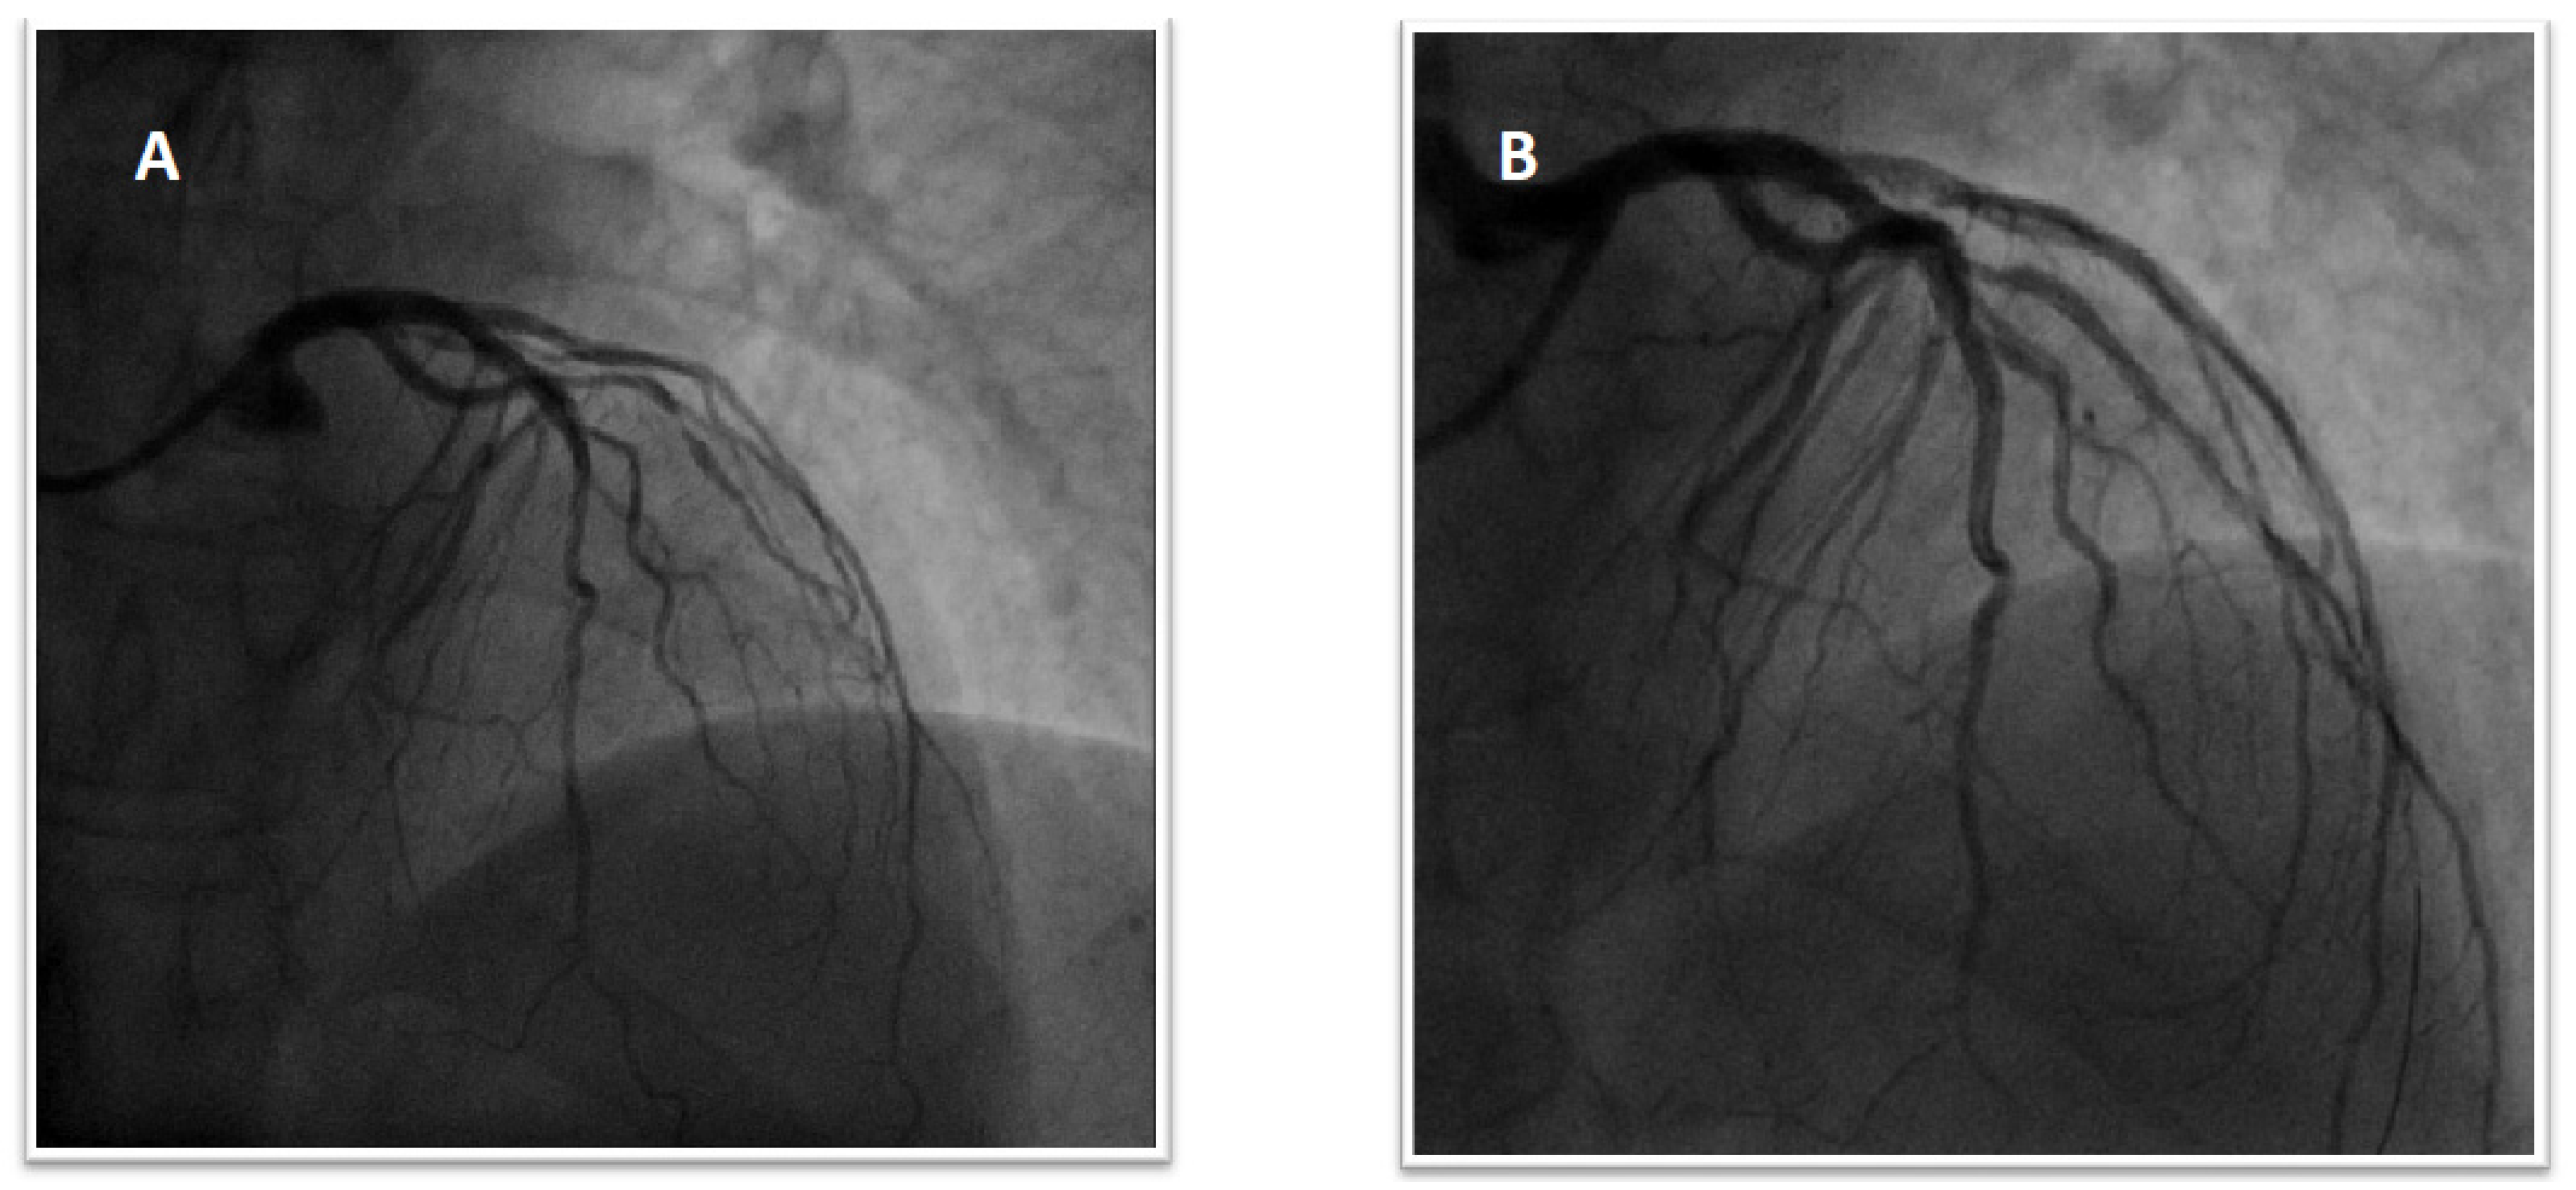

1.1. Patient 1

1.2. Patient 2